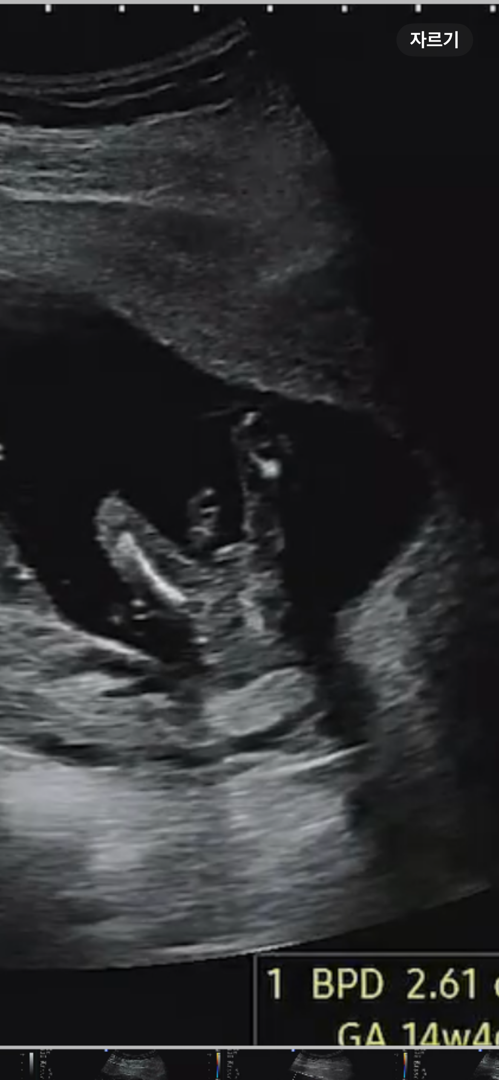

딸일까요??

딸인거같은데 아들인거같기도하고 궁금해서 올려봐요